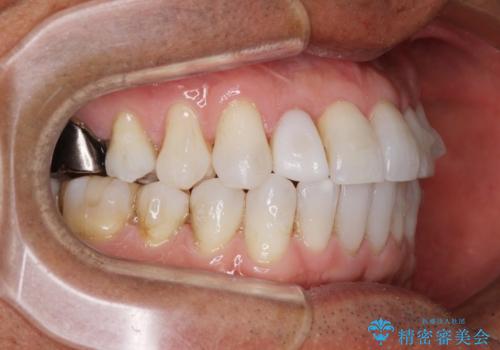

治療途中の前歯を治したい インビザライン矯正とオールセラミッククラウン

- 治療途中の前歯と上下前歯のデコボコ気にして来院された患者様です。

前歯のデコボコはインビザラインにより歯列を整え、その後に、前歯などをオーダーメイドタイプのオールセラミッククラウンにて補綴治療することとしました。

長時間のマウスピース装着に協力いただき、短期間で歯列をしっかりと改善することができました。

ホームホワイトニングを併用していただいたので、とても明るい口元に仕上がり、患者様には大変満足していただきました。